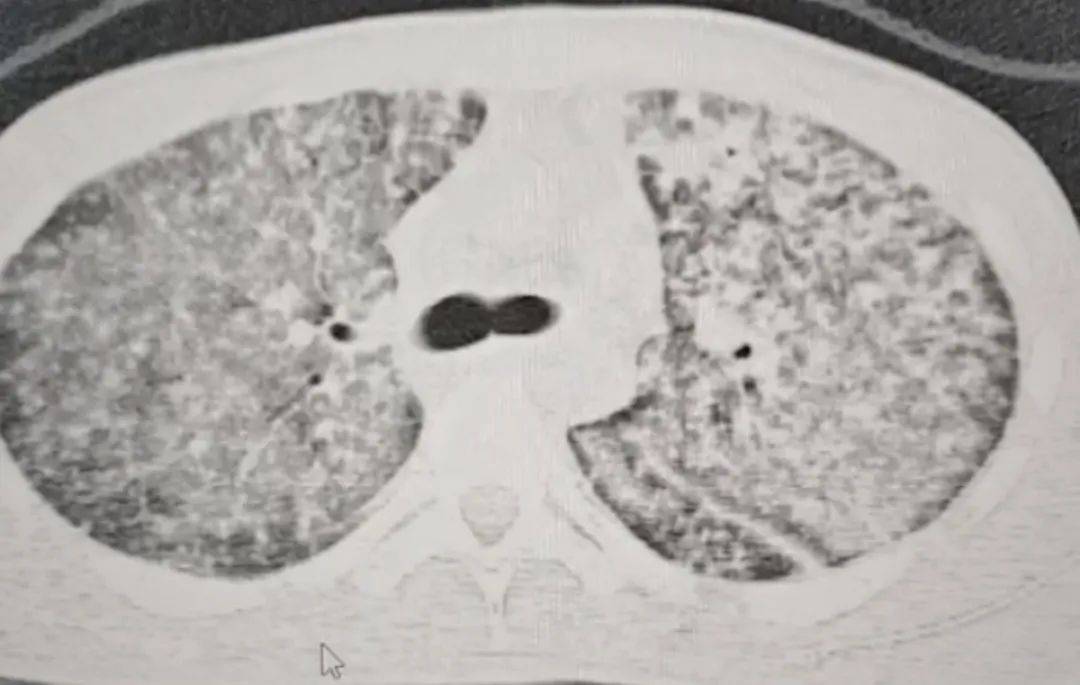

检查结果令医生大为震惊皇冠信用网开户 。肺部 CT 影像显示,小王的肺部几乎全白。

“他来我们医院时,我一看CT,双肺都呈现弥漫性病变,考虑白肺,情况十分危急皇冠信用网开户 。” 河南省胸科医院结核内科六/ 感染危重症病区主任梁瑞霞向大河报·豫视频记者讲述,小王因肺部感染引发了急性呼吸窘迫综合征。